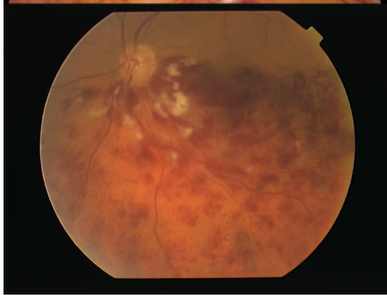

Name this condition

Proliferative DR

Clinical signs

Fluorescein angiography

Treatment

NVD, NVE, NVI

Fibrovascular tissue along the posterior surface of the vitreous

Fibrovascular tissue extending into the vitreous and adherent to the retina

Traction retinal detachment

Vitreous haemorrhage

Fluorescein angiograpy

Highlights the neovascularisation

Hyperfluorescence due to leakage from neovascular tissue

PRP

Surgical treatment of retinal detachment

Pars plana vitrectomy in vitreous haemorrhage

Anti VEGF treatment with caution

Follow up every 4 weeks 7